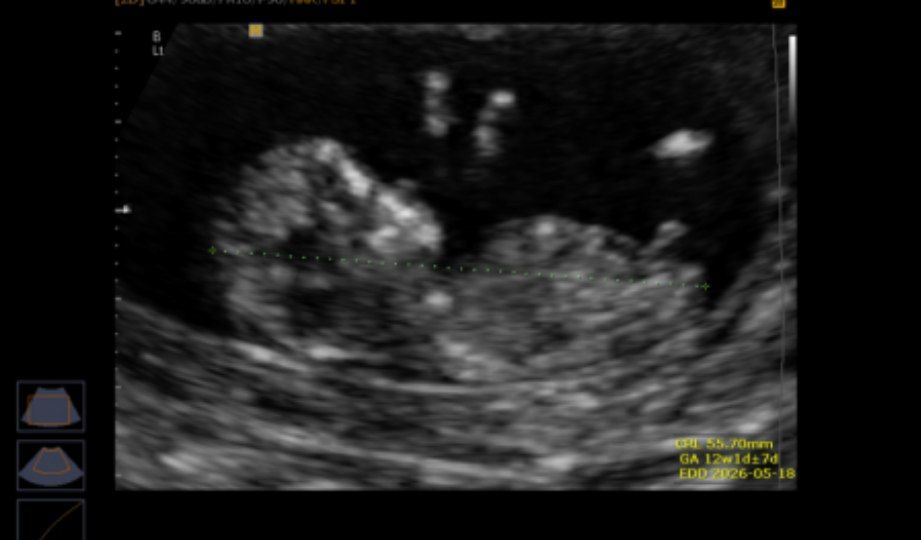

ارام67 مدیر استارتر عضویت: 1396/10/23 تعداد پست: 13590 سلام گلم غربالگری هم انجام دادی نمیدونم منظورت چیه سونو ان تی +ازمایش دادم از این کاربری دو نفر استفاده میکنن من و مامانم پس اگه تناقضی تو تاپیک ها دیدید تعجب نکنید